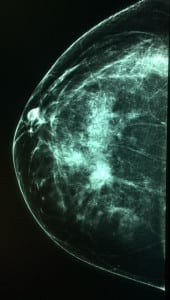

Caso 1.

((Mastografía digital: vemos en el tercio posterior un nódulo denso de márgenes espiculados, asociado a calcificaciones que varían en forma y densidad: relación a un cáncer ductal invasor))

((Imagen del mismo Nódulo por ultrasonido: se ve un nódulo sólido de márgenes angulados, altera el tejido que esta adyacente))